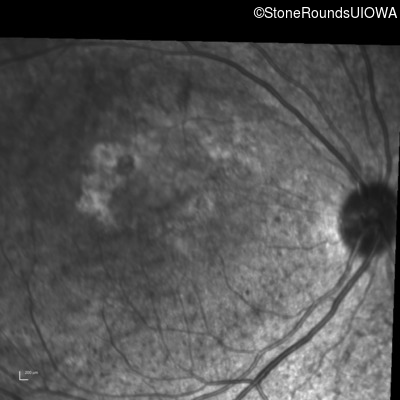

Infrared Fundus Photograph - Right - Count Fingers 2'

Exemplar

Infrared Fundus Photograph - Left - 20/25 -3